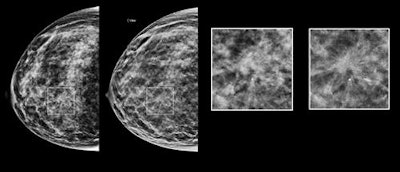

The researchers were "pleasantly surprised" by how well they performed using synthesized 2D DBT, Holt said. The synthesized images look different than conventional FFDM mammography, with an appearance that Holt characterized as having more contrast. But radiologists at the Graham Cancer Center are converts to the technology after seeing their numbers improve.